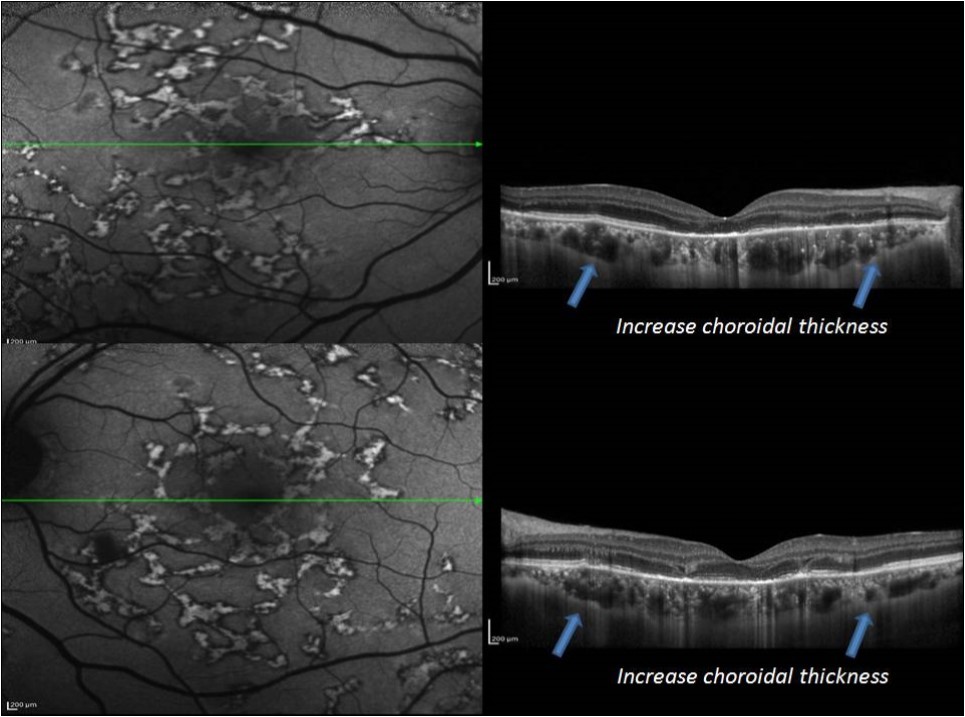

Figure 6.EDI-OCT in acute stage of MSC reveled increase choroidal thickness

In acute stage, SD-OCT showed hyperreflective areas involving the outer retinal layers which include retinal pigment epithelium (RPE), photoreceptor outer segment tips (POST), inner segment–outer segment (IS/OS) junction, external limiting membrane (ELM), and outer nuclear layer (ONL) with choroidal and intraretinal layer cells infiltrate. EDI-OCT showed increase choroidal thickness.

In an attempt to explore the extent of choroidal involvement during various phases of MSC, we prospectively studied the EDI-OCT changes in eyes with tubercular MSC.

Also our EDI-OCT observation demonstrated a diffuse choroidal thickening as well as localized changes in the deeper choroid beneath the active as well as healed lesions. This could suggest a choroidal involvement deeper to choriocapillaris. we believe that a diffuse increase in choroidal thickness may indicate an immunological trigger. The predominant and an early involvement of RPE may indicate the infective trigger which is go with Yeh et al who have hypothesized that RPE may be the site of primary insult and hence, more severely damaged in presumed tuberculosis-associated serpiginous-like choroidopathy based on the report of the isolation of mycobacterial DNA from RPE cells .11

Takahashi and associates used (EDI-OCT) to evaluate a 40-year-old woman with active, peripapillary SC with testing for known infectious causes of MSC was unrevealing in their study. They found that Prior to treatment subfoveal choroid was found to be markedly thickened (average713.3 ± 4.5 microns) and EDI-OCT localized the active peripapillary placoid lesions to just beneath the RPE, supporting published pathological studies showing diffuse choroidal inflammation with primary involvement of the choriocapillaris in areas of active placoid lesions in eyes with SC. Following treatment, subfoveal thickening decreased dramatically to 330 microns. This finding support the cilinical evidence that choroidal involvement is primary and the predominat insult in SC.12,13